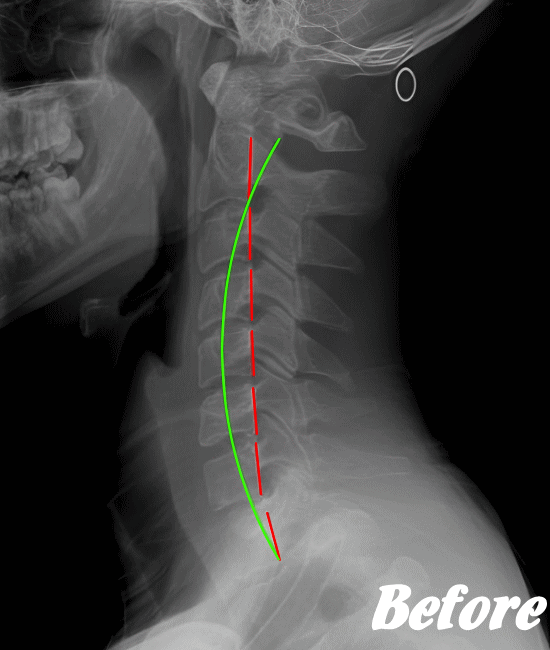

ストレートネックも、首に負担がかかりやすいので、注意が必要です。

病院では、まず問診票で首こり状態を診断します。症状により、レントゲンやCT、MRI、血液検査などを行います。特に他の病気の可能性が見つからないようであれば、頚性神経筋症候群と診断するようです。